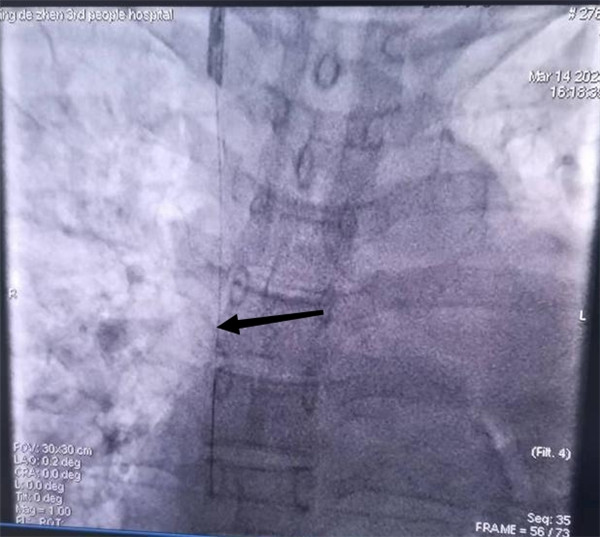

长期血液透析导管端引入导丝,在DSA下引入4.5mm球囊,在长期血液透析导管末端以压力泵反复扩张。经反复扩张后,血透管松动,与心脏黏连逐步被松解。轻柔拔除长期血液透析导管,将导丝留置在心脏。沿着导丝置入新血透管,并建立新的皮下隧道。拔除长期血液透析导管后保留导丝,在右锁骨中线下3cm处做一横行切口,从切口向导丝处分离皮下组织,剪断远端导丝,将新长期导管沿皮下隧道穿出,静脉撕脱鞘沿导丝置入颈内静脉,将长期血液透析导管沿撕脱鞘植入右颈内静脉,并行DSA下造影,缝合皮肤,手术顺利完成。术后造影提示新置入血透管末端在右心房上端,位置可、动静脉血液引流通畅。患者当日行无肝素血液透析,血流量240ml/min,透析过程顺利无异常。